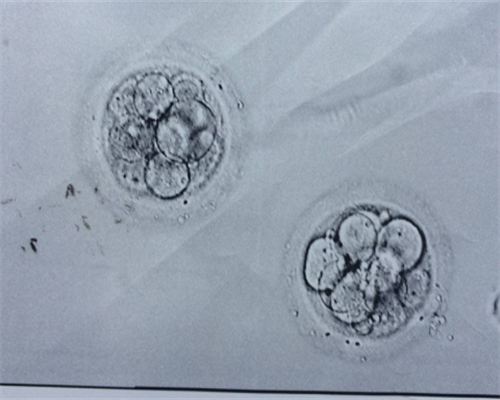

在进行三代试管婴儿治疗时,经过助孕受精后,医生会将优质胚胎移植到载体体内。一般来说在移植后的第3-5天,优质胚胎会完成着床过程。但并非所有的受精卵都能够成功着床,因此医生通常会将多个合适的胚胎同时移植,以增加成功率。

在进行人工受孕治疗时,选择合适的时间点进行胚胎移植非常重要。通常情况下,胚胎移植会在受精后的第3-5天进行。这是因为在此时胚胎已经发育到了适合着床的阶段。早期移植可能会导致胚胎无法正常着床,而过晚的移植则可能影响胚胎的发育和成功率。